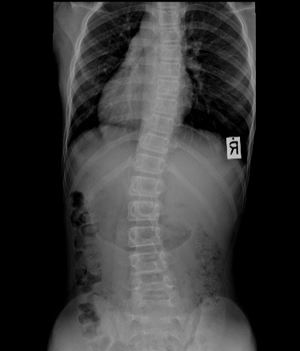

<ôÃßÃø¸¸ÁõȯÀÚ X-RAY>

Á¤»óÀûÀΠôÃß´Â Á¤¸é¿¡¼­ º¸¾ÒÀ» ¶§ ÀÏÁ÷¼±ÀÌ¸ç ¿·¿¡¼­ º¸¾ÒÀ» ¶§¿¡´Â °æÃß¿Í ¿äÃß´Â ¾ÕÀ¸·Î ÈÖ¾î ÀÖ°í ÈäÃß¿Í ÃµÃߺδ µÚ·Î ÈÖ¾î ÀÖ½À´Ï´Ù.

º¸Åë ôÃß°¡ 10µµÀÌ»ó ÈÖ¾î ÀÖ´Â °æ¿ì¸¦ Ãø¸¸ÁõÀ̶ó°í Çϸç 40µµ ÀÌ»ó ÈÖ¾îÀÖ´Â °æ¿ì¿¡´Â ±³Á¤Ä¡·á¸¸À¸·Î ÇØ°áÀÌ ¾î·Á¿ï ¼ö ÀÖ½À´Ï´Ù.